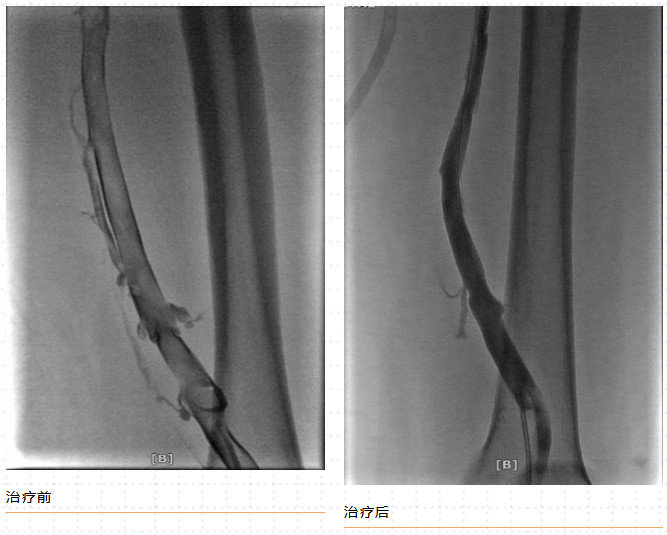

一经确诊,治疗越早越好,这也可避免晚期的严重后遗症。我们可以通过抗凝、溶栓、取栓、机械吸栓等办法综合处理血栓,即一站式完全微创的血管介入手术,仅通过1~2处“针眼”,便可清除血栓,术后第二天即可出院。